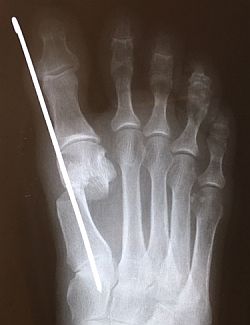

For those of you who prefer evaluating newer surgical procedures with a bit more published research behind them, look at the European orthopedic literature on MIS bunionectomy. Most of these procedures are variations on the same technique, namely a through-and-through metatarsal neck osteotomy with aggressive lateral translation of the capital fragment along with a unique stabilization of the capital fragment using a 2mm K-wire as shown here.

Post-op X-ray of SERI Bunionectomy |

There are several of these published studies dating back to the early 1990s, but the most expansive is by Giannini, et al. in International Orthopedics, September 2013 entitled "A Minimally Invasive Technique for the Surgical Treatment of Hallux Valgus; Simple, Effective, Rapid, Inexpensive (SERI)" (PMID 23820757) with 1,000 cases. At first glance, this technique seems prone to non-union, though in this study, none were reported. Dorsal malunion was observed though only in 8 cases.

I’ve been doing open bunionectomy techniques since I started practice in 1988, though with robust studies on MIS such as these, I’ve started doing the SERI technique over the past several months. It is trickier to perform than you might expect, though patients do experience very little post-op pain and minimal swelling compared to open techniques, and they do appreciate the smaller scar.